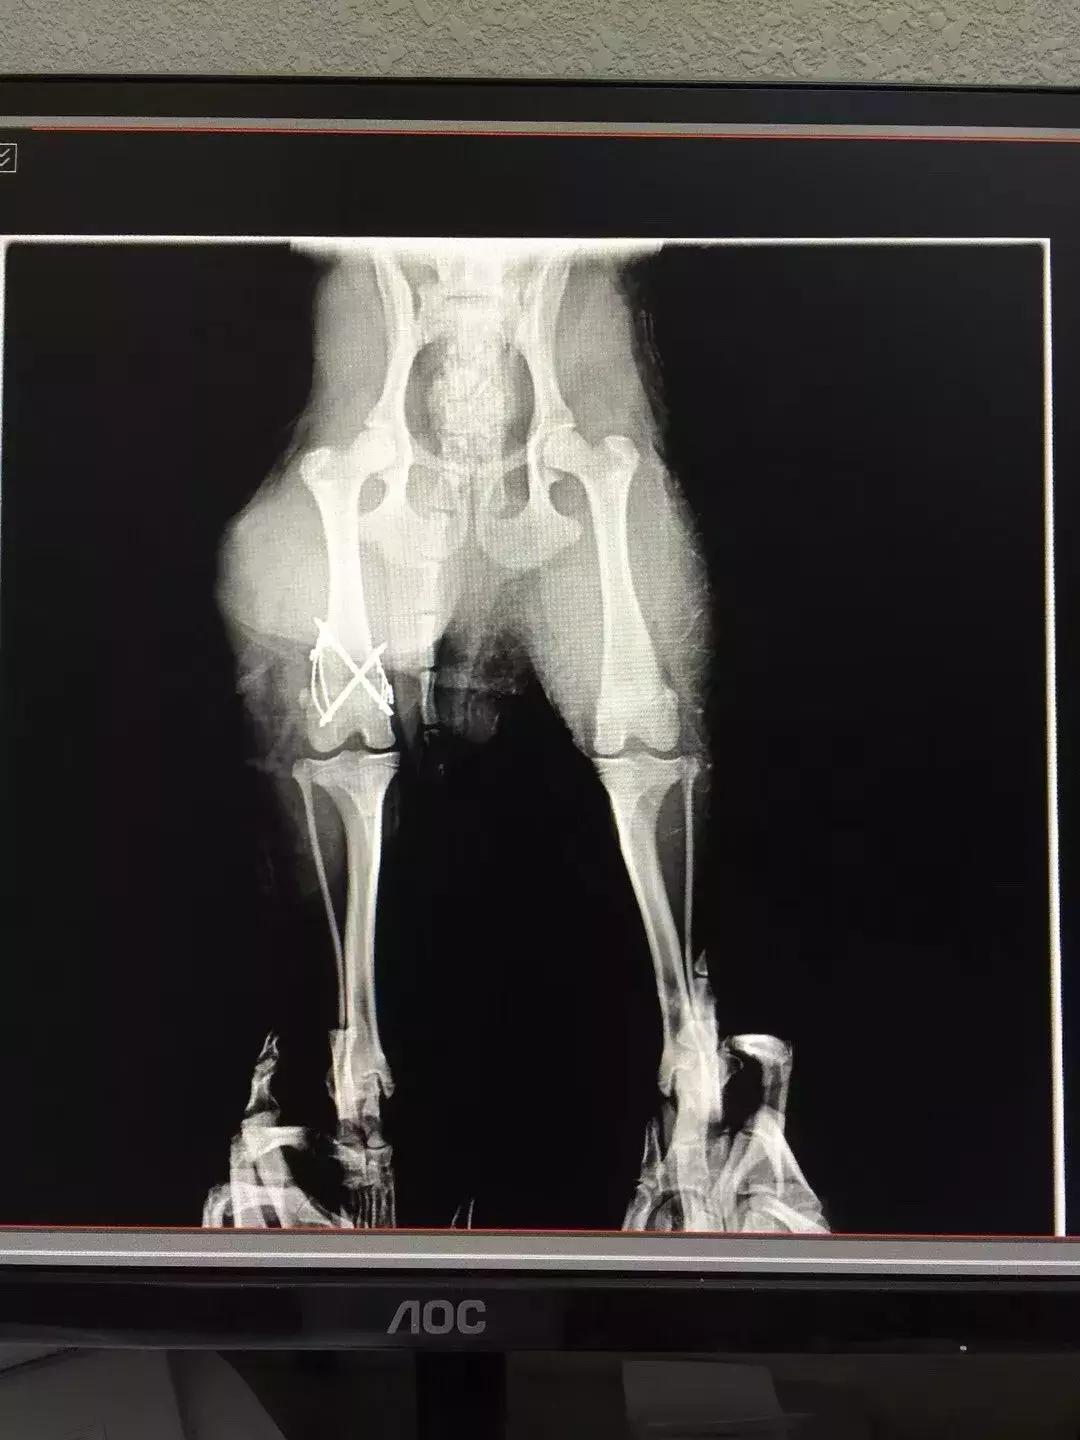

术前x-ray显示,六一的骨折为 左前肢肱骨中远段骨折 ,骨折类型为横骨折。

术后X线片

六一小朋友的年龄仅有3个月,体重仅1kg,对于这样的幼猫,陈旧性骨折发生二次骨折的内固定手术无疑是一个严峻的挑战。六一的主治医生张海峰院长使用接骨板板对六一进行了骨折的内固定。